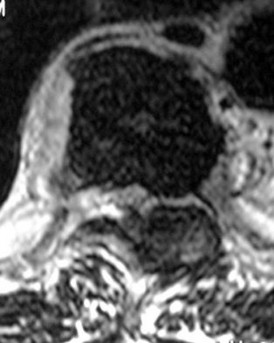

A 55-year-old Asian male presents with progressive clumsiness in his hands and a wide-based gait. Imaging reveals ossification of the posterior longitudinal ligament (OPLL) from C3 to C6. The sagittal MRI shows that the OPLL mass crosses the K-line (K-line negative), and the cervical spine has 15 degrees of local kyphosis. Which surgical approach is most appropriate?

Explanation